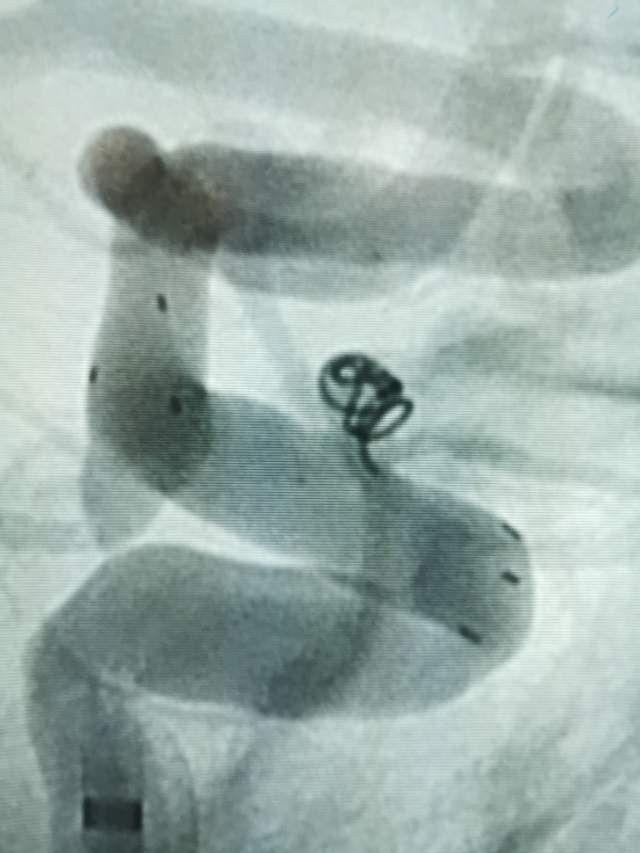

44岁盐城帅哥,因“头痛3天”发现静脉窦血栓合并“颅内动脉瘤“来诊。颅内动脉瘤之一是瘤体累及眼动脉的相对宽颈微小动脉瘤(2.5mm),此部位动脉瘤存在破裂出血的风险,而且静脉窦血栓的治疗也会加重此风险,有必要同步先消除这个潜在的风险。病变累及眼动脉,如果治疗过程中受到累及存在失明风险,需要重点保护。最终,采用一个支架一个圈的“简约模式:花费少,效果好”结束手术,眼动脉保留良好。